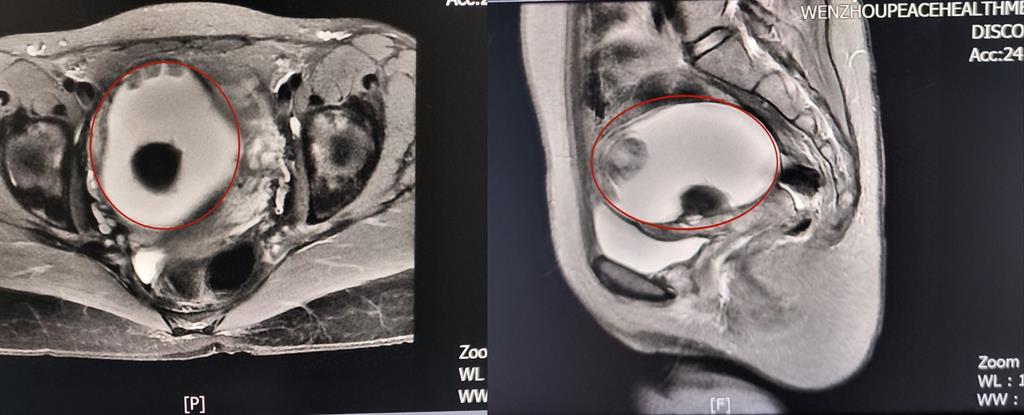

前不久,溫州某高校外籍教師A女士來(lái)到和平國(guó)際醫(yī)院體檢與健康管理中心進(jìn)行深度體檢。B超提示“子宮右側(cè)附件區(qū)囊性塊,大小約82*79*88mm”和平國(guó)際醫(yī)院婦科主任醫(yī)師方軼萍發(fā)現(xiàn),A女士還有三項(xiàng)腫瘤標(biāo)志物數(shù)據(jù)超標(biāo)(甚至高出正常值兩倍)。

卵巢腫瘤?為進(jìn)一步明確診斷,A女士在方主任建議下做了增強(qiáng)磁共振,影像結(jié)果提示:盆腔右側(cè)團(tuán)塊狀占位伴多發(fā)成熟脂肪成分大小約89*100*71mm,考慮畸胎瘤可能性大。謎團(tuán)逐漸解開(kāi),原來(lái)那個(gè)“怪胎”可能是畸胎瘤在作祟。

回家考慮后,A女士決定來(lái)和平國(guó)際醫(yī)院手術(shù)治療。“畸胎瘤大部分是良性,而且患者未婚未育,評(píng)估后我們決定采用微創(chuàng)的治療方案——腹腔鏡下畸胎瘤剝除術(shù)。”方主任講到,這樣不僅創(chuàng)傷小,還能保護(hù)患者的生育能力。

因腫物與周圍組織粘連致密暴露困難,這極考驗(yàn)主刀醫(yī)生的經(jīng)驗(yàn)和專業(yè)技術(shù)。為避免腫瘤破裂及血管損傷,和平國(guó)際醫(yī)院婦科團(tuán)隊(duì)主任醫(yī)師方軼萍、副主任醫(yī)師周婷在腹腔鏡下精細(xì)操作,完整切除囊腫,術(shù)中快速冰凍病理檢查結(jié)果證實(shí):成熟型囊性畸胎瘤(良性)。

術(shù)后,在醫(yī)護(hù)人員的精心護(hù)理下,A女士傷口愈合良好,于術(shù)后第3天出院調(diào)養(yǎng)。